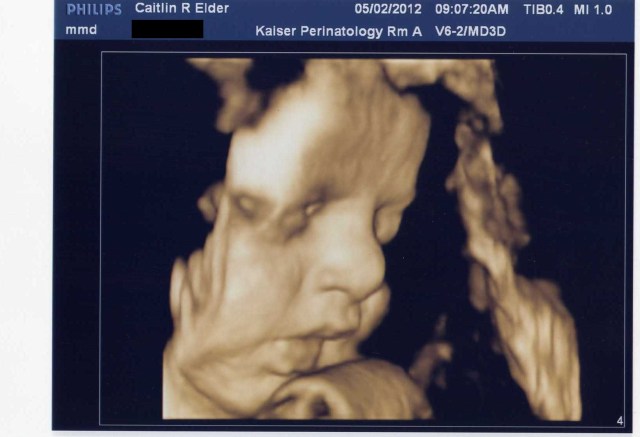

I can’t end this post with Mo-bug because it’s supposed to be about #2, so here’s one last (little bit fuzzy) 3-D image of her cute little face. We’ll be able to compare these pictures to the real thing in T-minus 8-ish weeks. Oh man, all of a sudden that doesn’t seem like a very long time. I better go clean something…or eat some ice cream. Hmm…She does have quite a bit of weight to put on…I definitely choose ice cream.